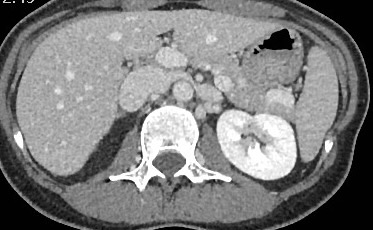

🙌🏻 Webinaire du <a href="/JURI_Fr/">Junior Radiologie Interventionnelle</a> ce soir 😎

🩻 Syndrome de congestion pelvienne avec le Pr <a href="/gsoulez/">Gilles Soulez</a>

Patiente avec douleurs pelviennes chroniques.

La phlébographie montre une incontinence de la veine gonadique gauche.

Quel syndrome sous jacent suggère le scanner ?👇